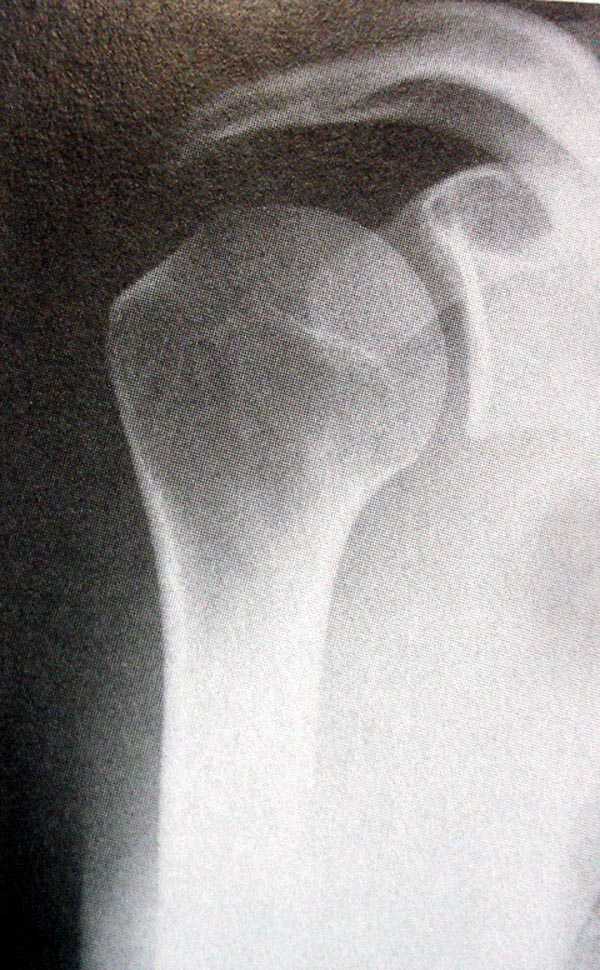

Закрытый оскольчатый перелом хир. шейки плеча со смещением |

Коллеги, мы тут рассходимся во мнениях. Больной, 30 лет, оскольчатый перелом шейки плеча со смещением, примерно две недели. В травмпункте закрытую репозицию делать не стали, от открытой также отказались, дескать, смещение незначительное, срастется и так, руку на косынку и отпустили.Пришел через две недели к нам. Состояние на снимке.Как лучше лечить дальше, как думаете? Консервативно, оперировать? Успех закрытой репозиции сомнитетелен, на мой взгляд.

Проблема -- смещение отломка, неудовлетворительный контакт, угроза нарушения функциональности (ограничение движений, если срастется так). Мнения разделились примерно пополам: лечить консервативно/прооперировать. Кроме того, пациент жалуется на сильные боли в суставе, которых, как мне кажется, на пятнадцатый день быть не должно.

Нельзя по одной проекции судить о положении отломков

Рентгенологические исследования проксимального отдела плеча состоит из прямого, бокового и аксиальных видов. Если имеются сложные переломы тогда рекомендуется Томография, а так в большинстве случаев достаточно бывает стандартных снимков.

Независимо от условий (нежелание рентгентехника или отсутствие пленок) необходимо добиться рентгенограмм, особенно аксиальной, потому что одна проекция не гарантирует, что не пропущен вывих в плечевом суставе.

Для принятия решения и исследования обычно достаточно пару дней, а здесь третья неделя, начало консолидации метафизарной части, надо спешить!